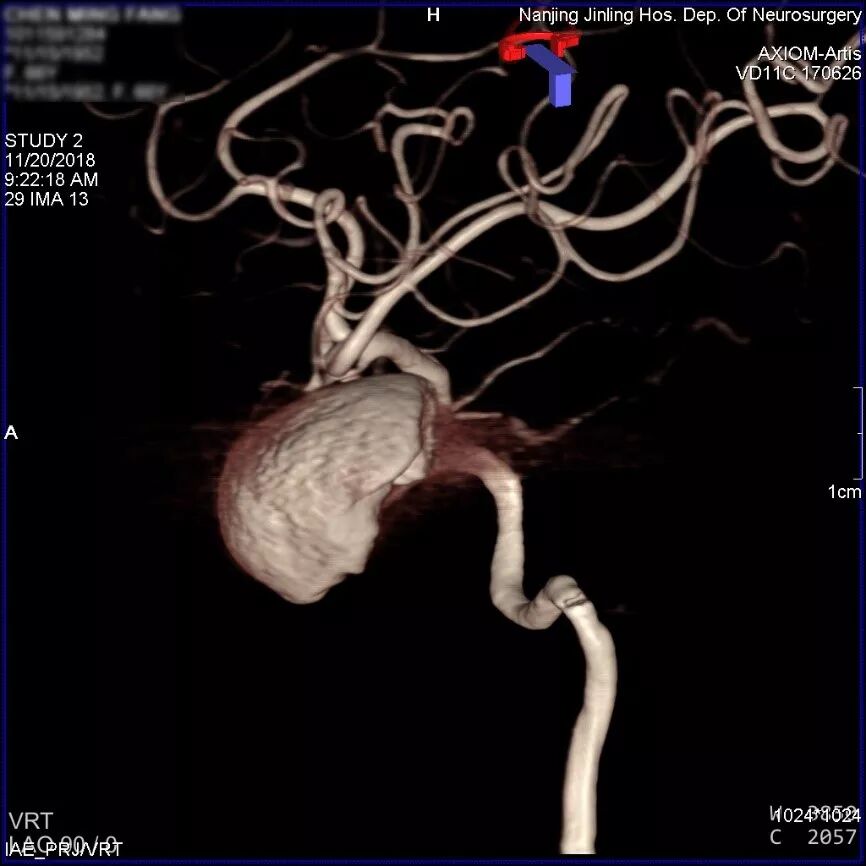

左侧颈内动脉海绵窦段巨大动脉瘤,余颅内血管未见明显异常。

患者取平卧位,气管插管全麻,右侧股动脉穿刺,置入6F 70cm长鞘至左侧颈总动脉,5F Navien中间导管在Marksman引导下超选至动脉瘤近端,行3D旋转造影显示:左侧颈内动脉海绵窦段大型血栓性动脉瘤。

显影部分动脉瘤大小约31.6*23.1mm,瘤颈宽6.4mm,载瘤动脉远端直径约为2.93mm,近端约为2.89mm。根据造影情况决定行血流导向装置置入术,选择Pipeline Flex 3.0mm*35mm。